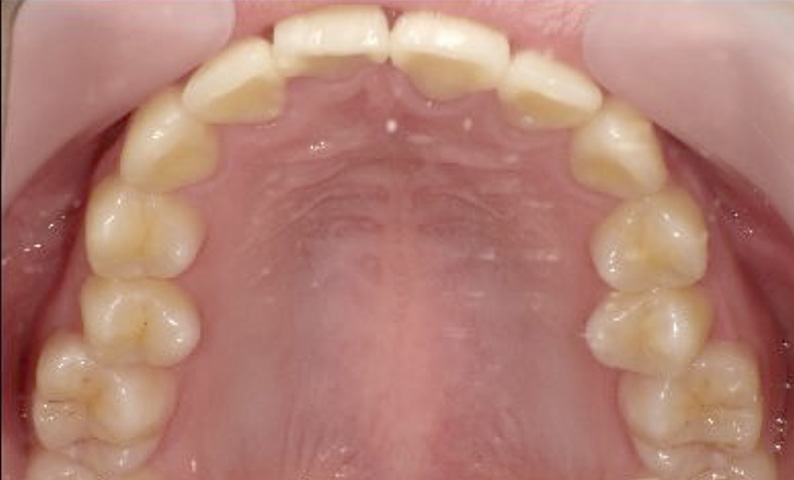

症例_022 上顎だけの部分矯正

治療期間:9ヶ月金額:30万円+税女性前歯のガタガタ前歯のガタガタ上の前歯だけ

| Before | After |